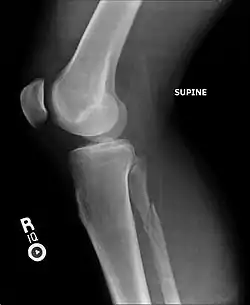

| Radiograph showing a Maisonneuve fracture of the proximal fibula | |